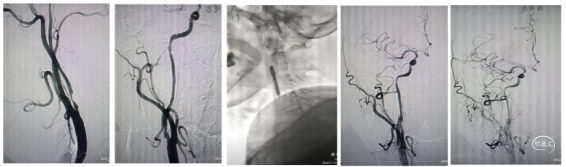

球囊穿梭:8F导引导管到达颈总动脉远端,微导丝携带微导管通过颈内起始部闭塞,2.5*15mm冠脉球囊扩张闭塞部,泄压的同时辅助6F中间导管通过狭窄到达C1以远。

踹马桶抽吸清理颈内动脉滞留血液:清理颈内滞留血液,抽出0.5 cm大小血栓,微造影M1段有血栓残留。下图2、3、4

支架取栓开通远端血管:微导丝回头弯置于M2段,将微导管置于M2段,输送4*30 SLitaire支架,抽拉结合取栓后造影血管通畅,未见明确血栓逃逸。下图5

颈内动脉狭窄血管成形:

负压抽吸回撤中间导管与颈总动脉,造影显示颈内动脉C1段重度狭窄。在C1段置入5mm保护伞,通过保护伞导丝输送4*30球囊预扩张后植入8-6一40颈动脉支架。撤出保护伞。

撤出保护伞再次造影显示颈内血管又不显影了,考虑血管痉挛可能。泥鳅导丝导引6F中间导管在颈内动和支架内抽吸未抽出血栓,但血管再次通畅。

推注替罗非班10mL,罂粟碱30mg,等待15分钟造影血流通畅,结束手术。